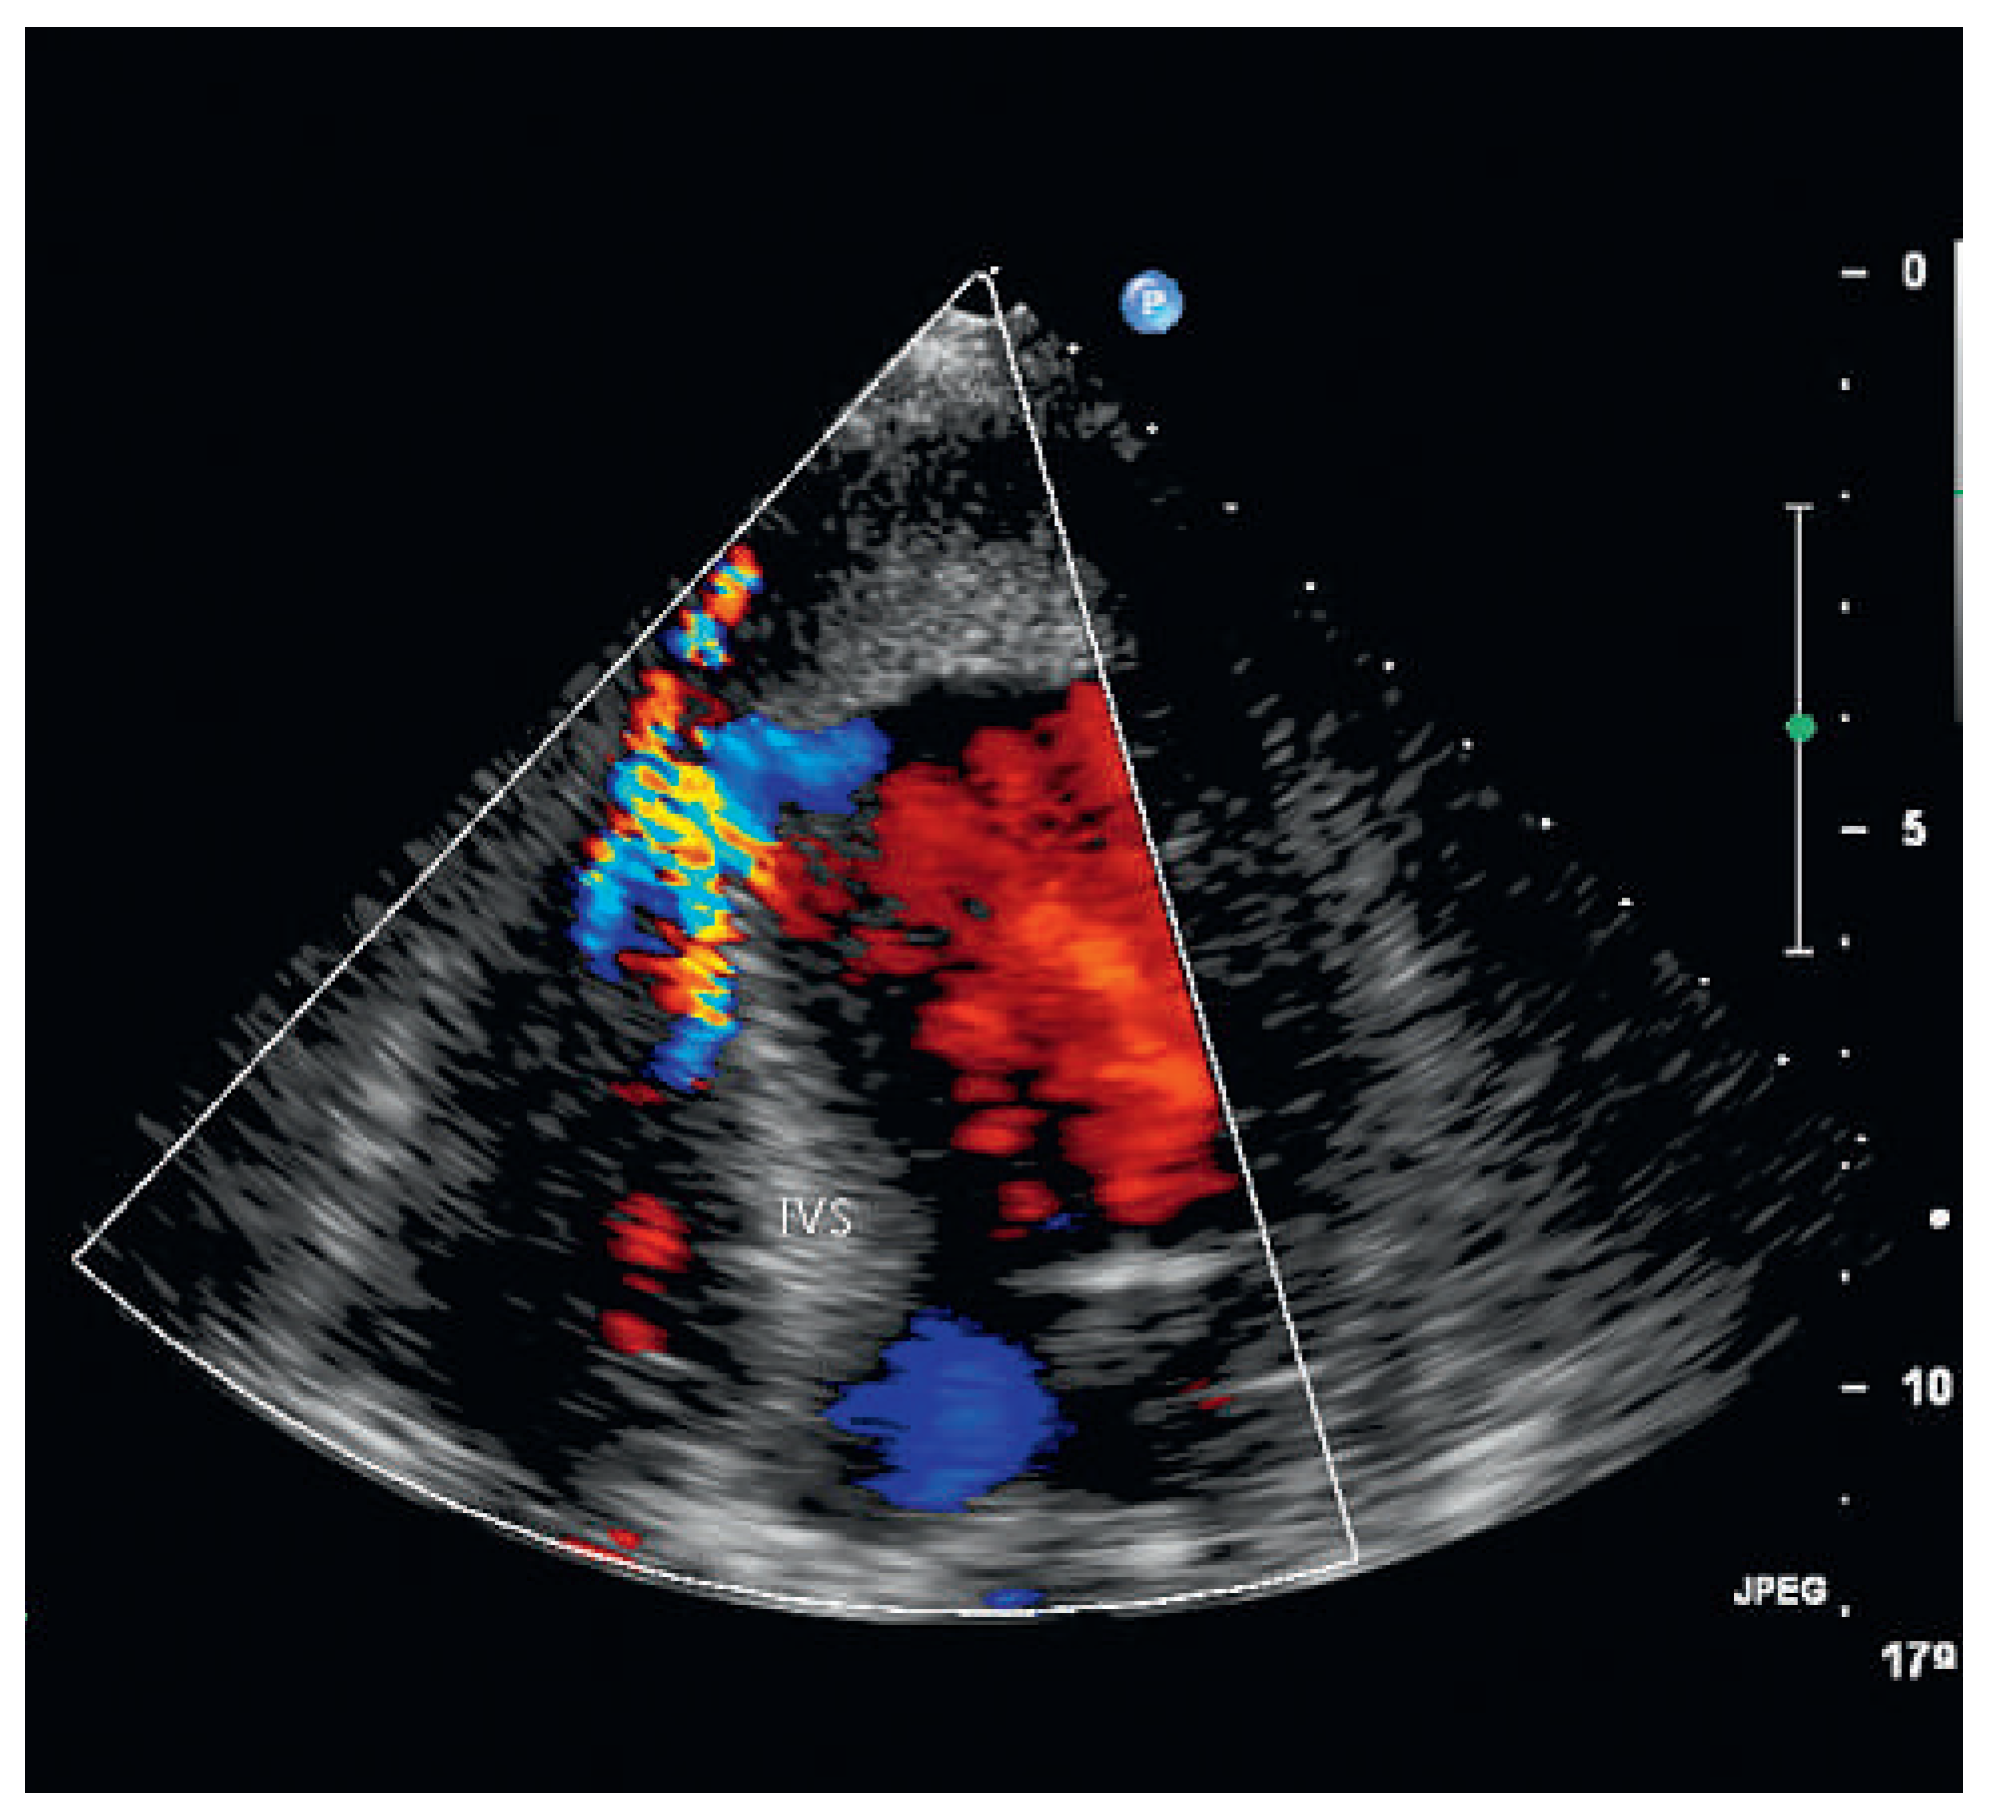

A 87-year-old female patient was hospitalised for decline in general health status, fatigue and oedema following a fall two weeks earlier. On no occasion did the patient experience chest pain or shortness of breath. The blood pressure and heart rate on admission were 113/79 mm and 80 bpm Hg respectively. Cardiopulmonary auscultation revealed a harsh, loud holosystolic murmur most audible along the left sternal border and radiating to the base, apex and right parasternal area, with accentuation of the second heart sound and crepitus rales across all lung fields. Bilateral ankle oedema was present without distention of the jugular veins. The ECG was compatible with subacute anterior and inferior myocardial infarction. Echocardiography showed severely depressed left ventricular function in the presence of apical and anteroseptal dyskinesia and septal rupture with bidirectional shunt on colour Doppler. In addition, an apical thrombus and severe aortic stenosis with severe pulmonary hypertension were noted. In light of the patient’s age and the echocardiographic findings it was decided not to institute active treatment, and during the echocardiographic examination the patient developed profound cardiogenic shock and died.

Figure 2. Colour Doppler with ventricular septal rupture (left to right shunt). IVS = interventricular septum.